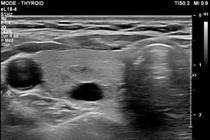

Nang tuyến giáp là một trong những rối loạn phổ biến của tuyến giáp, hình thành khi trong tuyến giáp xuất hiện một hoặc nhiều túi chứa dịch.